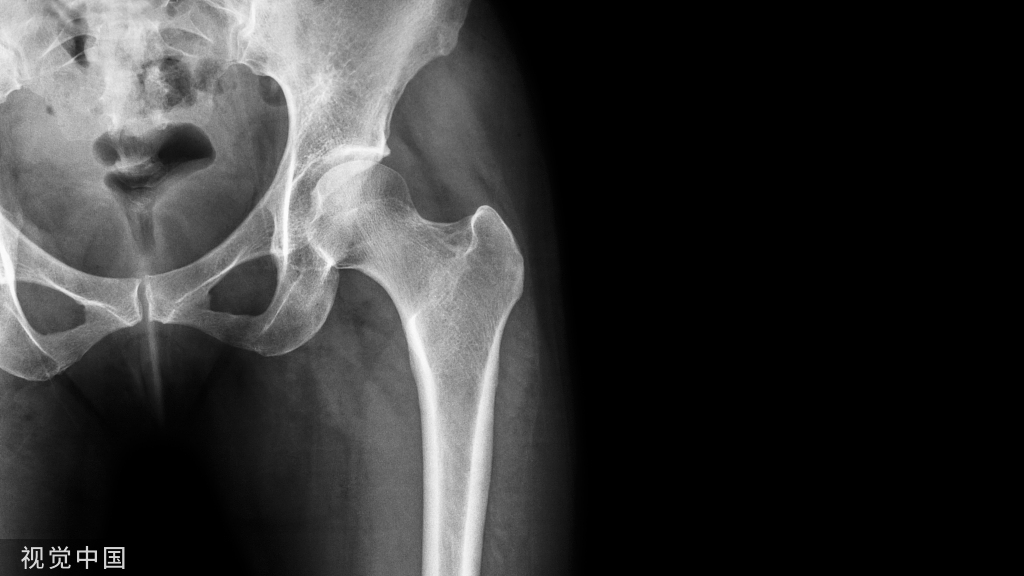

多段骨折

对于多段骨折(C2),先打钢板两末端锁定钉,再以1-2枚普通皮质骨螺钉垂直骨干长轴通过钢板固定中间骨段;再在骨段两旁各打一枚保护螺钉(锁定)。最后,在保护螺钉与末端螺钉间视情况再各加打1-2枚锁定钉。仍需注意遵循长钢板、少螺钉的应力分散原则(如下图示)。

严重粉碎骨折

对于严重粉碎骨折(C3),按照AO理念,首先尽可能间接复位、桥接固定;相对稳定、二期愈合。

先打钢板两末端锁定钉,再靠近粉碎骨折区两端各打一枚锁定钉以增加骨折区的稳定性。最后,在稳定螺钉与末端螺钉间视情况再各加打1-2枚锁定钉。仍需注意遵循长钢板、少螺钉的应力分散原则(如下图示)。粉碎骨折钢板工作距离一般约占钢板总长度的1/3为宜。